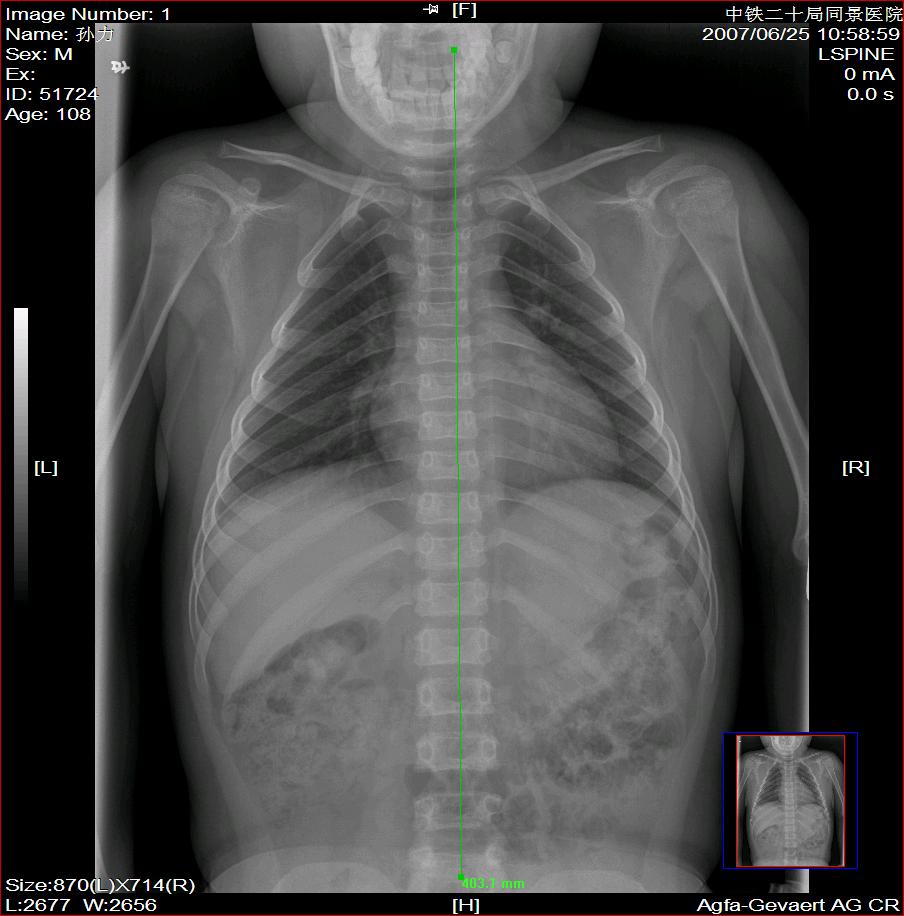

标题: X2504:M17Y,高中生,身高不足1.2米,智力正常 [打印本页]

标题: X2504:M17Y,高中生,身高不足1.2米,智力正常

年龄17岁,身材矮小(1.2m),全身骨骼发育迟缓,骨骺线仍较宽,但全身骨骼骨质正常,智力正常。

符合侏儒症。

骨结构正常,骨骺线与17岁不符,豆状骨未见,相当7-8岁骨龄,结合智力正常,垂体性侏儒可能大。

考虑垂体侏儒的可能。依据1骨龄延迟,骨胳结构正常,智力正常。与甲状腺功能不足区别呆小症病人长骨及骨垢有改变,骨垢较正常小。椎体变扁。考虑垂体侏儒症。

各部比例在正常范围,为均称型侏儒,可见于1、垂体性侏儒。2、致密性骨发育不全。3、turner氏综合症。本例骨密度正常,皮质边界清,显然不支持致密性骨发育不全,未见掌骨征阳性和指骨优势,turner氏综合症,可基本除外,剩下的只有垂体性侏儒了,建议垂体mri进一步检查,确定诊断。以上主要参考曹来宾教授发表的论文,侏儒症的临床x线分析

全身骨骼发育迟缓,骨骺线仍较宽与年龄不符。考虑垂体性侏儒可能大。